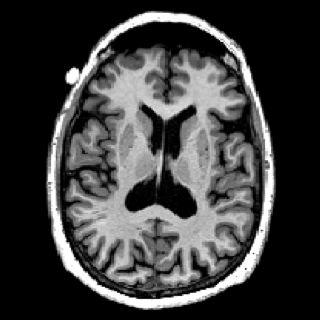

Recalage#

L’objectif est d’effectuer le recalage de l’image irm2.png sur l’image irm1.png. On sait que l’image a subi une rotation autour du centre de l’image, en plus d’autre dégradations. Le critère de similarité est l’erreur quadratique moyenne (EQM) entre les images \(f_1\) et \(f_2\), toutes deux de taille \(M \times N\) :

• Implémentez l’optimisation de l’EQM, avec une simple recherche exhaustive, pour déterminer le meilleur angle de rotation pour effectuer le recalage.